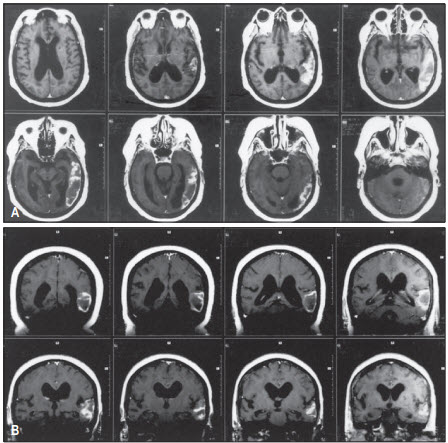

Hình. MRI của bệnh nhân thất ngôn Wernicke gây nên bởi tổn thương thùy thái dương. A, hình ảnh cắt ngang; B, hình ảnh cắt dọc.